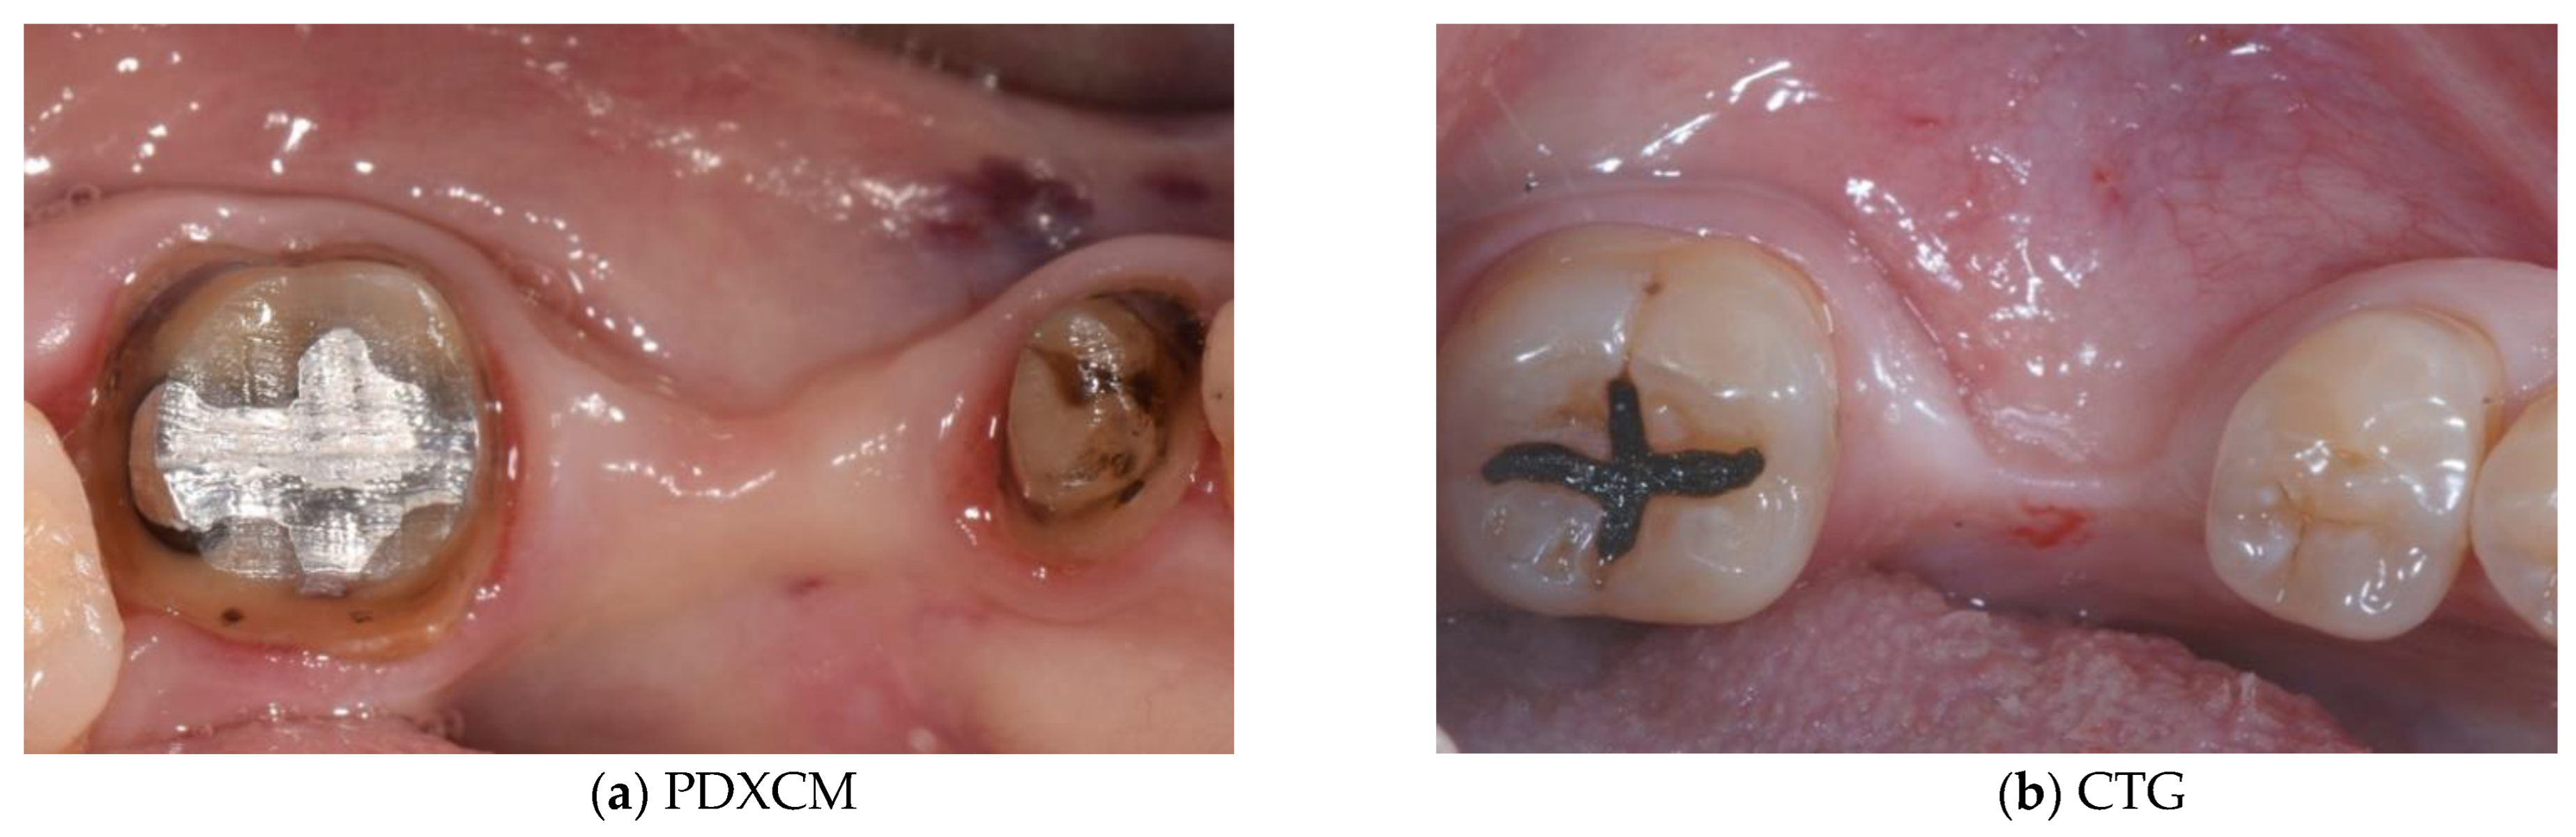

| Papi et al. [27] | 12 patients | Prospective cohort study | 12 months | N R | PDXCM: 1.25 |

| Zafiropoulos et al. [38] | 27 patients | Prospective, randomized examiner-blinded controlled clinical study | 6 months | N R | PDXCM: 1.06 |

| Stefanini et al. [39] | 10 patients | Case series | 12 months | PDXCM 0.65 ± 0.41 | PDXCM: 1.2 ± 0.18 |

| Papi and Pompa 12 [40] | 12 patients | Prospective pilot cohort study | 12 months | PDXCM: 4.32 | N R |

| Schmitt et al. [41] | 14 patients | Controlled clinical trial | 6 months | N R | PDXCM: 0.30 ± 0.16 |

| Verardi et al. [42] | 24 patients 24 implants | Prospective study | 6 months | PDXCM 1.33 ± 0.71 | N R |